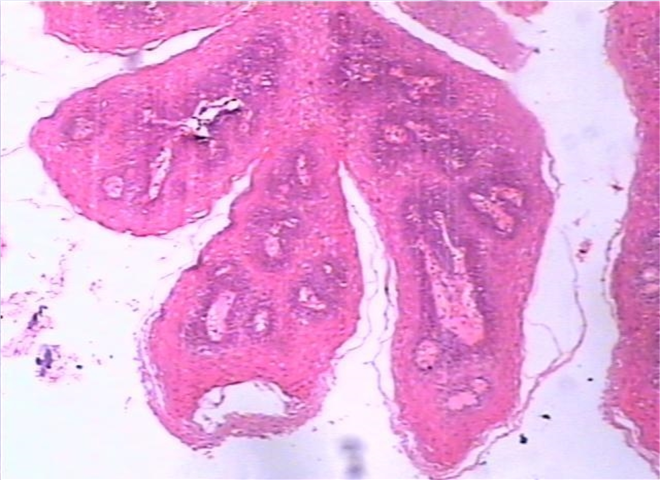

03_肿瘤基础课